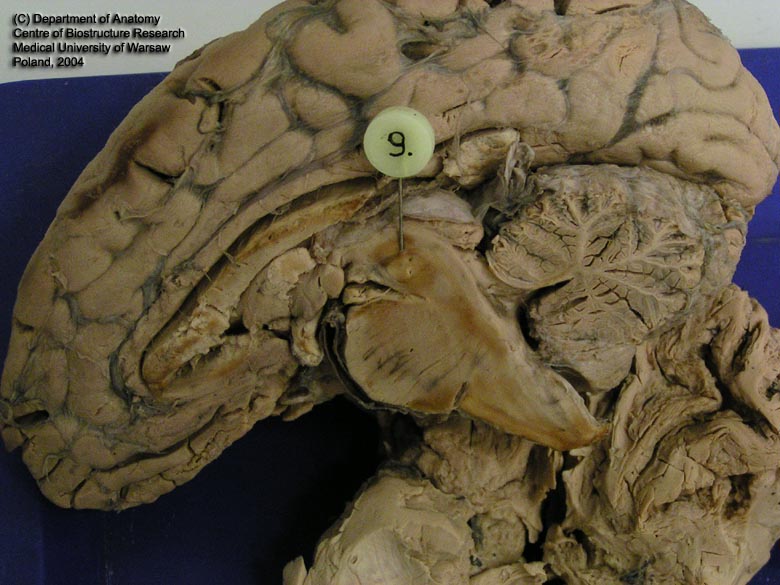

hippocampus dex.

ventriculus IV

Aquaeductus mesencephali

Thalamus Dex.